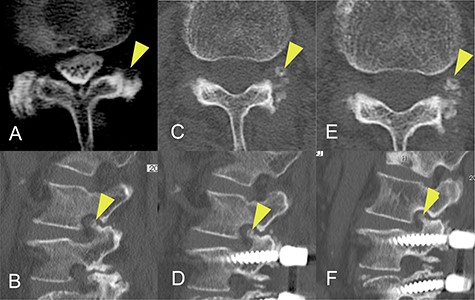

Progression of ossification of the ligamentum flavum (OLF) on computed tomography (CT) images obtained before onset of radiculopathy. (A) OLF was not found on a CT scan obtained 8 years earlier. (B) A CT image obtained 20 months earlier shows a small isolated area of OLF in the foramen. (C, D) A CT image acquired 4 months earlier shows that the area of OLF had grown slightly and was integrated with the superior articular process. (E, F) A CT image obtained at the time of surgery shows further expansion of OLF.

CT images acquired a few months before the onset of radiculopathy had shown a small isolated area of ossification, suggesting that the ossification site had gradually expanded to include the superior articular process over a period of months (Fig. 3).

The changes in CT findings over time in this case (Fig. 3) confirm that the ossification was initially confined to the ligamentum flavum but gradually expanded to the point where it constricted the nerve root at the foramen. However, our review of the literature did not yield any reports of OLF as a cause of radiculopathy at the foramen. Furthermore, although there are some reports on the classification of OLF, most did not include an isolated type. Sato et al. proposed that thoracic OLF be classified as lateral, extended, enlarged, fused or tuberous [14]. Mori et al. subsequently recommended a modified classification system based on whether OLF was small, medium, large, extra-large or central-type [6]. However, Saiki et al. identified four types of OLY, namely, spiny, placoid, nodular and isolated [15]. They also identified that 1% were of an isolated free type, which they defined as a form of ossification that is free in the ligamentum flavum and has no continuity with the articular processes. We consider that our case could be classified as the isolated free type of OLF originally described by Saiki et al. and suspect that this rare type of OLF may have been overlooked in more recent studies, particularly those using CT images. Furthermore, the radiographic and CT images obtained before the onset of radiculopathy in this patient were valuable in that we were able to confirm progression of OLF before the onset of symptoms.